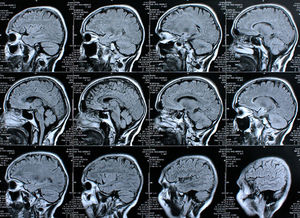

Sie sind hier: Startseite Nachrichten Gesundheit Omega-3-Fettsäuren wirken nachweislich positiv auf das alternde Gehirn Gehirn-Scans. Bild: pixelio.de, Rike

Gehirn-Scans. Bild: pixelio.de, Rike